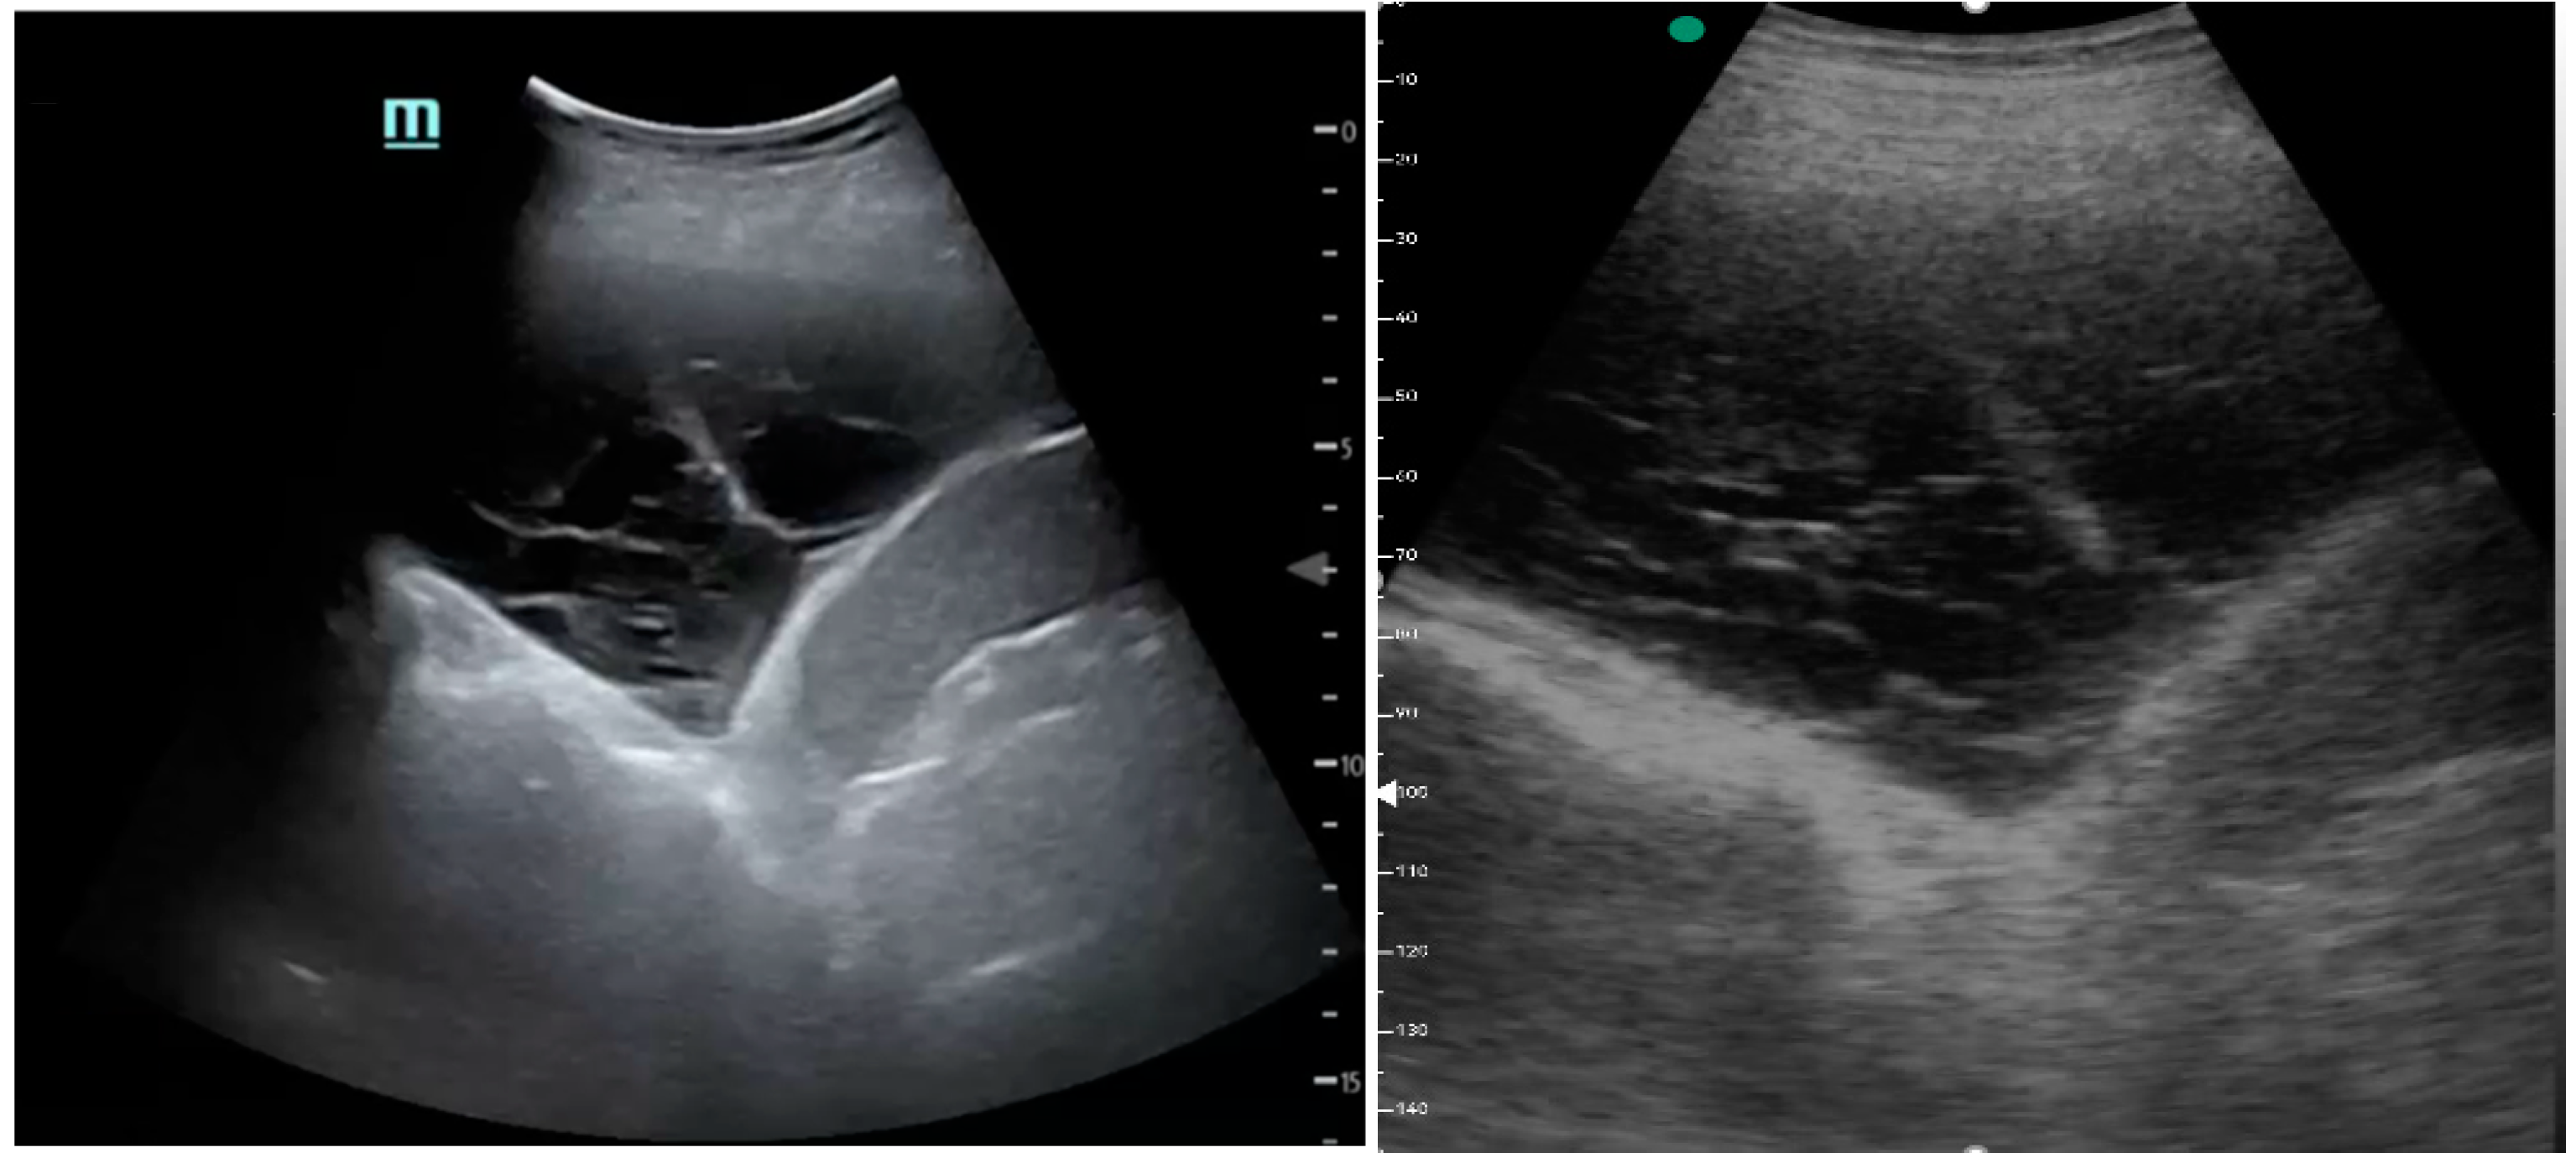

Figure 1, Figure 2 and Figure 3 exhibit characteristic examples of ultrasound still images from the videos captured via a standard ultrasound (left side) and portable handheld device (right side). Quality may slightly differ from that of the videos as these are still images.

Figure 2.

Complex pleural effusion with septation.